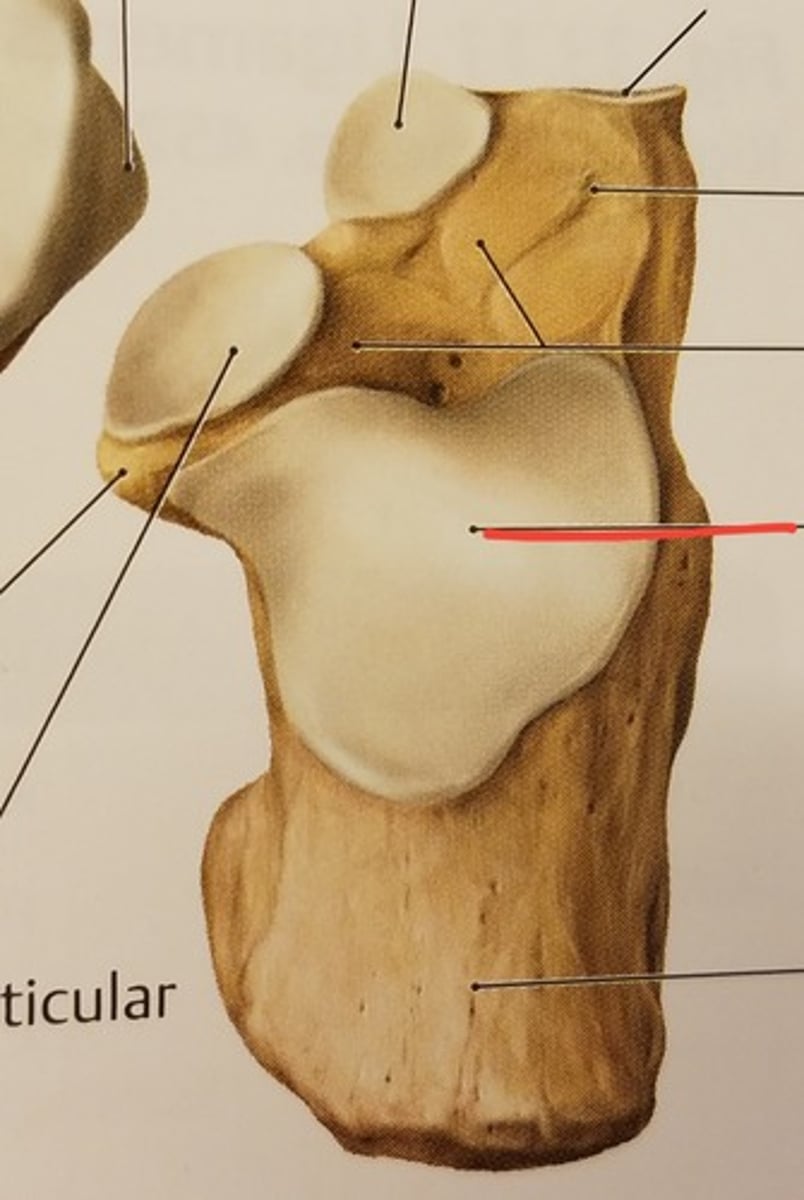

Patella

Apex

inferior surface for patellar ligament

Base

superior surface for quadriceps tendon

Medial articular surface (for medial condyle of femur; smaller)

green

Lateral articular surface (for lateral condyle of femur; bigger)

green